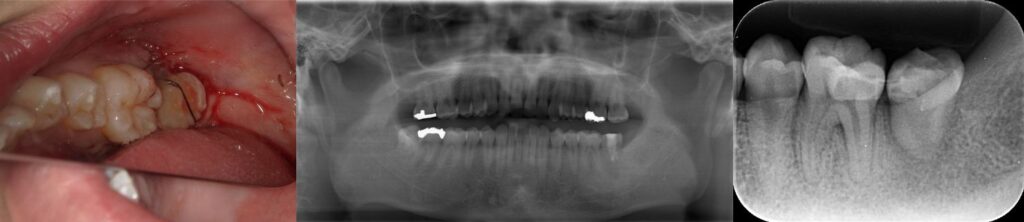

移植歯に対するエムドゲイン塗布および形状確認(抜歯時に破折してないかなど)

右上8を左下7へ移植完了

この後、根管治療、治療に必要な神経開口部の被覆を行いました(経過2年の状態は良好)